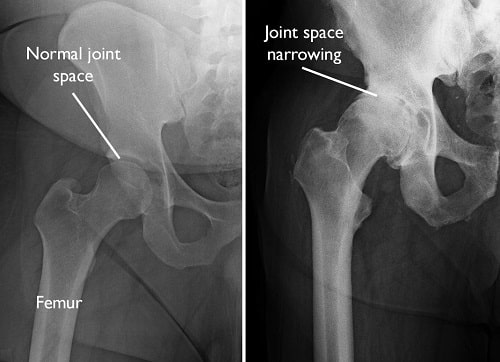

The abnormality found in this X-Ray:

Dislocation

Osteoarthritis